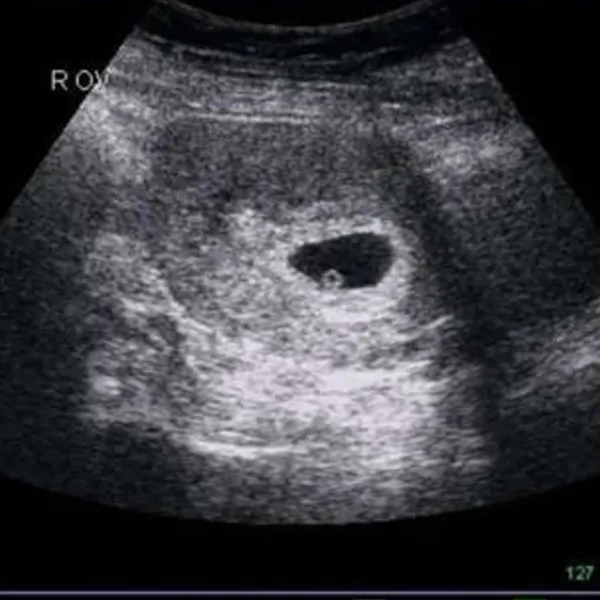

1. Hành trình của noãn sau rụng trứng

Ở nửa đầu chu kỳ, hormone FSH và LH kích thích một nang trứng phát triển. Khoảng ngày 14 (trong chu kỳ 28 ngày), nang vỡ, giải phóng noãn vào loa vòi tử cung. Từ khoảnh khắc này, chiếc trứng mỏng manh chỉ có “cửa sổ sinh học” 12–24 giờ để gặp tinh trùng. Nếu cuộc hội ngộ không diễn ra, trứng nhanh chóng bước vào tiến trình thoái hoá sinh lý:

- Rối loạn phóng noãn: hội chứng buồng trứng đa nang (PCOS), cường prolactin, suy buồng trứng sớm làm noãn kém trưởng thành.